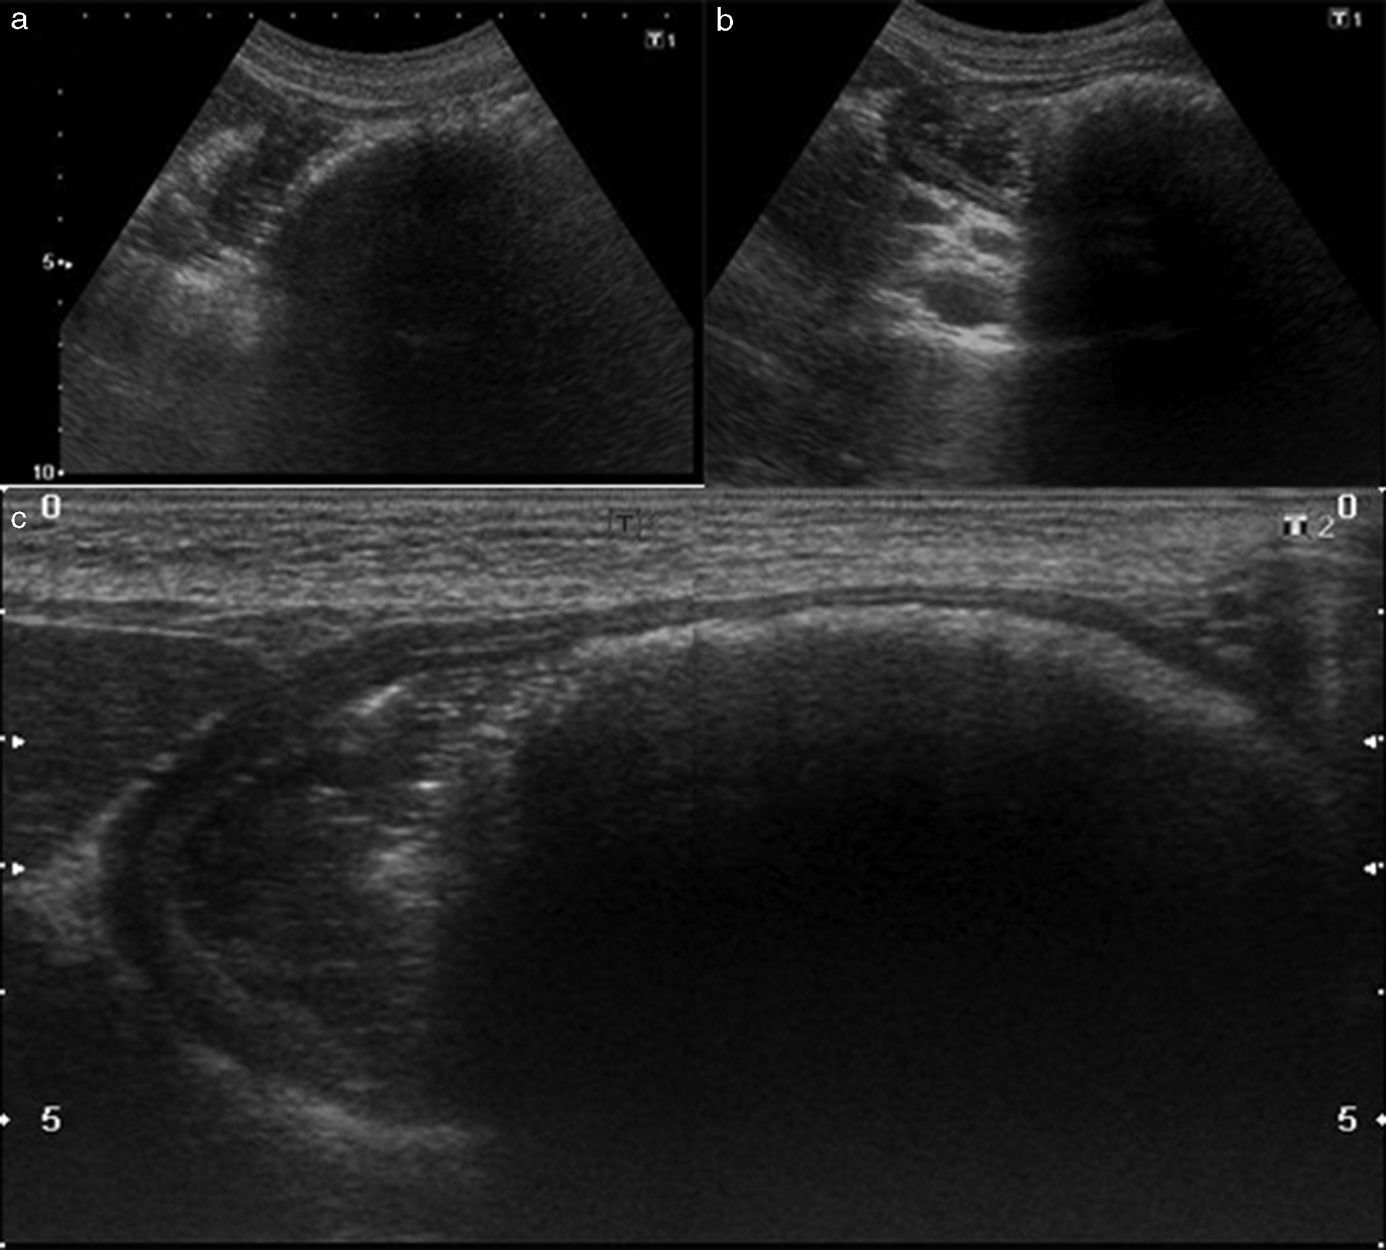

Las radiografías abdominales manifestaron una masa radiopaca ocupando y moldeando la cámara gástrica (fig. 1) y la ecografía de abdomen evidenció una masa gástrica intraluminal con borde hiperecogénico y sombra acústica posterior, sugestiva de bezoar (fig. 2). Por su parte, la neumo-TC mostró una masa con densidad de partes blandas heterogénea y aire en su interior, que moldeaba la cámara gástrica y era compatible con tricobezoar (figs. 3 y 4). Este último estudio permitió, además, realizar la medición y volumetría de la lesión a fin de obtener la mayor cantidad de información posible para el planeamiento terapéutico. El diagnóstico se confirmó mediante una endoscopia alta.

Ecografía de abdomen que evidencia una masa gástrica intraluminal con borde hiperecogénico y marcada sombra acústica posterior, altamente sugestiva de Bezoar. (a) Vista con transductor de 3,5MHz y estómago vacío. (b) Vista con transductor de 3,5MHz y estómago lleno de agua. (c) Foto panorámica con transductor de 7,5MHz con estómago lleno de agua.